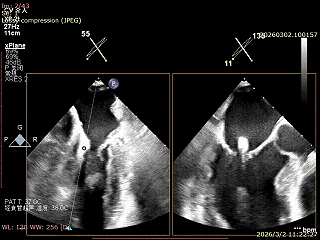

患者为房间隔缺损术后合并功能性二尖瓣反流(FMR),病变位于二尖瓣2区偏3区,因既往ASD修补史(可降解房间隔缺损封堵器),致房间隔穿刺区域存在瘢痕粘连、穿刺难度增加,于靠下靠后位置穿刺,避开房间隔缺损封堵伞,其余病变解剖结构相对简单;术前制定手术策略,拟使用1把XTR行二尖瓣修复,术中克服瘢痕粘连难点成功完成房间隔穿刺,穿刺点距二尖瓣瓣环平面3.1cm,将XTR‑CDS送入左心房,通过”A”旋钮旋转180度借高度,LVOT切面夹子严重Huge,使用”+”旋钮一键消除Huge,通过操控“M”旋钮将二尖瓣夹精准定位于2区正上方,完成弹道测试及Orientation调整后,于2区将夹子送入左心室,顺利捕捞并夹持瓣叶后缓慢闭合夹臂;TEE检查示二尖瓣反流充分降低至微量,二尖瓣双孔组织桥稳定,跨瓣压差2mmHg,肺静脉逆流明显改善,手术安全顺利结束。

穿刺可用高度不足,通过”A”旋钮旋转180度借高度,此时LVOT切面夹子严重Huge

使用”+”旋钮一键消除Huge

XTR弹道测试

3D enface 完成Orientation调整

成功捕捞瓣叶并夹持

缓慢关紧夹臂